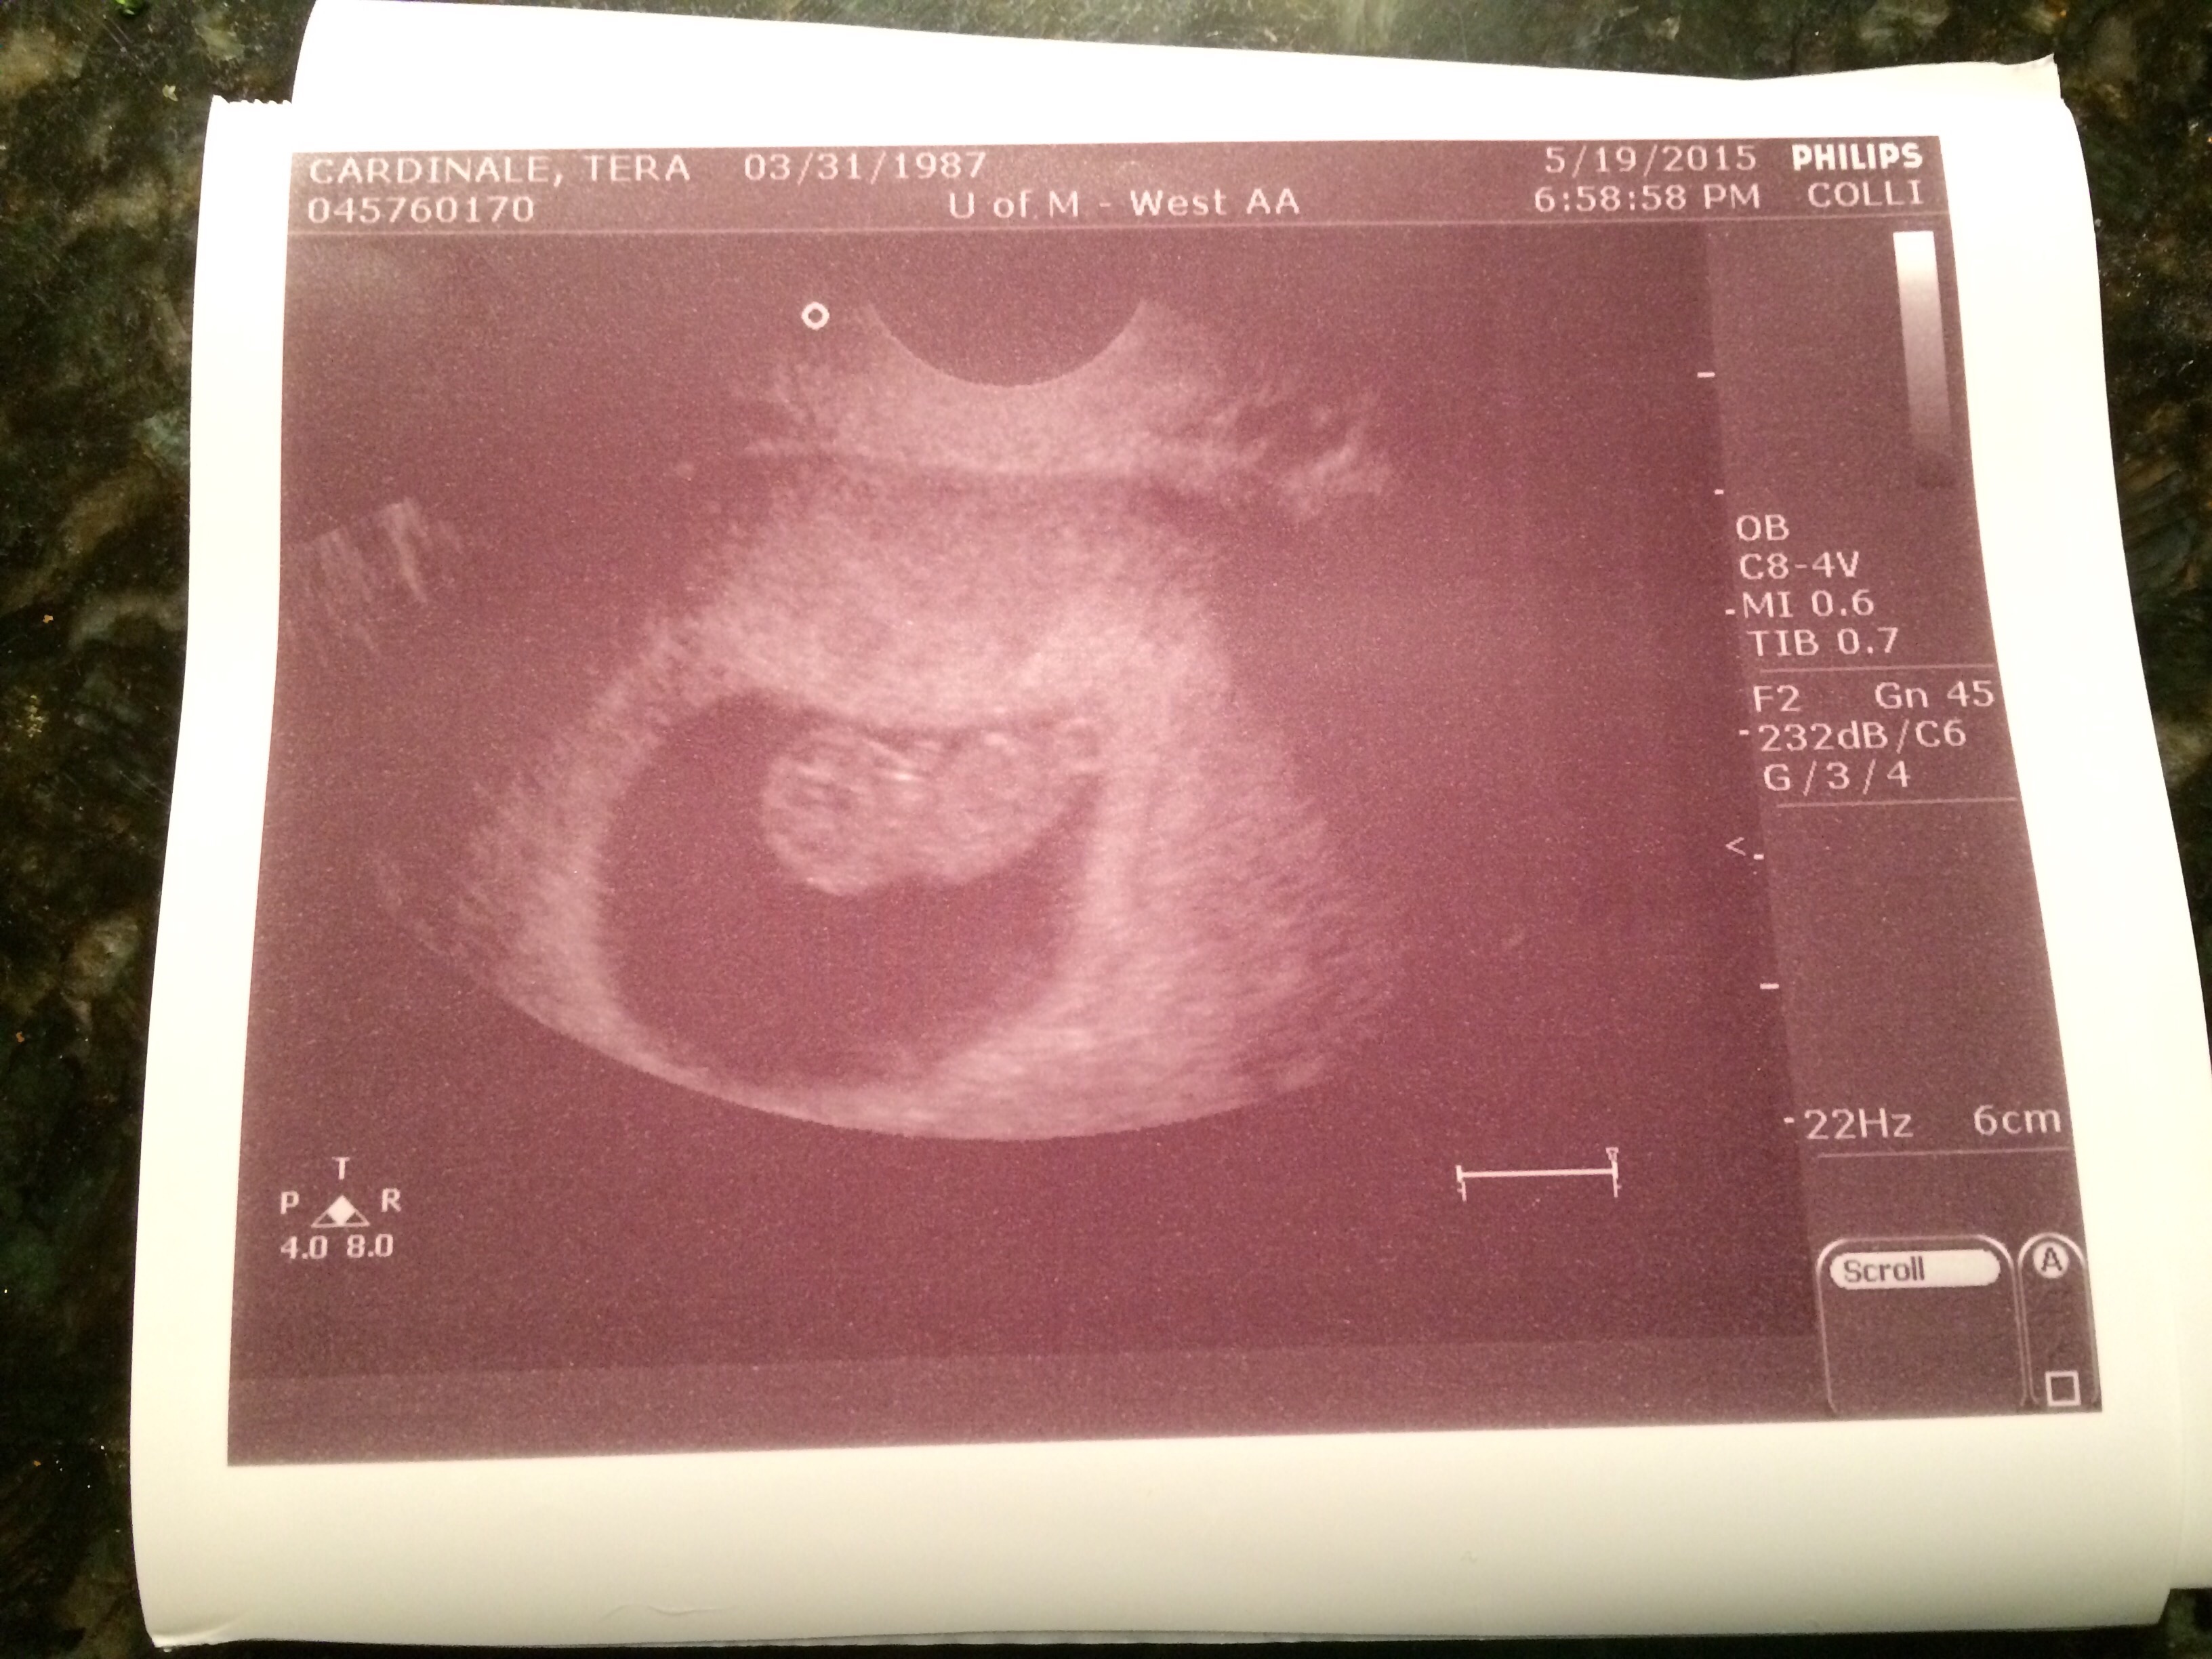

U/S is somewhat hard to see but head on left and arm bud sticking up, waving hi :-h Hi buddy!

Edit: oops, sideways pic confusion